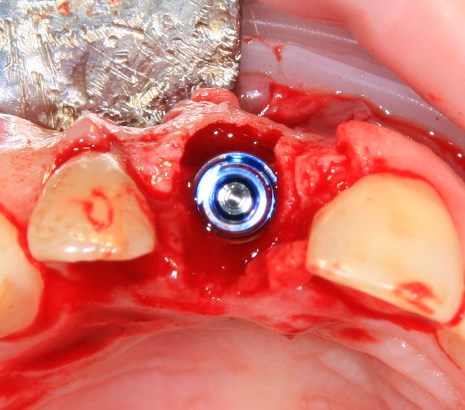

Немедленная имплантация — оптимальное решение в любой клинической ситуации